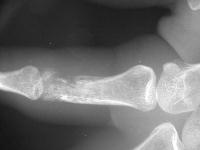

Radiographic erosive changes of the proximal phalanx.

Biopsy: soft tumor, extending subcutaneous to intramedullary.